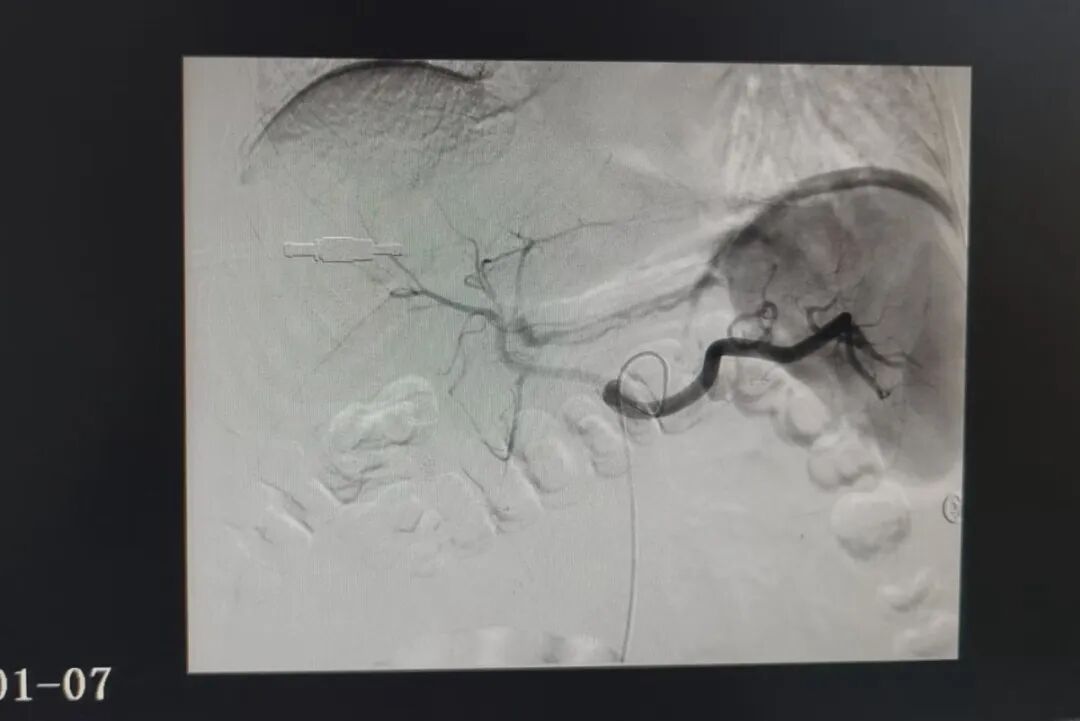

据悉,该患者为男性,58岁,既往有鼻咽癌并肝、肺、骨、左颈部淋巴结多发转移病史,此次因“右上腹疼痛8小时”入住消化内科。入院查体显示,患者急性面容,表情痛苦,腹部膨隆,上腹部腹肌稍紧张,全腹部压痛、反跳痛,肝区有叩击痛,肠鸣音正常。入院后完善相关检查,影像结果提示存在转移瘤可能,需进一步检查明确病因。在住院期间,患者突然黑便,血压急剧下降,脸色白得像纸,整个人陷入休克边缘,生命体征极不稳定。他的血红蛋白仅剩32g/L(正常成年男性为120-160g/L),相当于全身血液濒临“流干”!这对于肝癌并多发转移、身体状况本就十分脆弱的患者而言,生命已悬于一线。危急关头,消化内科团队立即行急诊胃镜检查,发现十二指肠巨大溃疡并出血。内镜医生凭借精准识别与敏锐判断,考虑是动脉出血,未行常规的内镜下止血处理,而是通过完善增强CT检查,确认是十二指肠上动脉假性动脉瘤破裂,这就像体内有一颗随时会爆炸的“小炸弹”。

面对如此凶险复杂的病情,消化内科团队迅速启动应急预案。排除相关禁忌症后,介入团队立即为患者行选择性动脉造影术+胃十二指肠动脉栓塞术。通过微导管精确找到了出血的动脉——那个破裂的“小炸弹”。凭借一根细如发丝的导丝、一次精准的栓塞操作,成功为患者止住了大出血。这场紧急抢救的微创手术,没有开刀,没有大创口,仅通过患者大腿根部一个针眼大小的穿刺点,便完成了高难度的血管“拆弹”,把患者从死亡线上拉了回来。